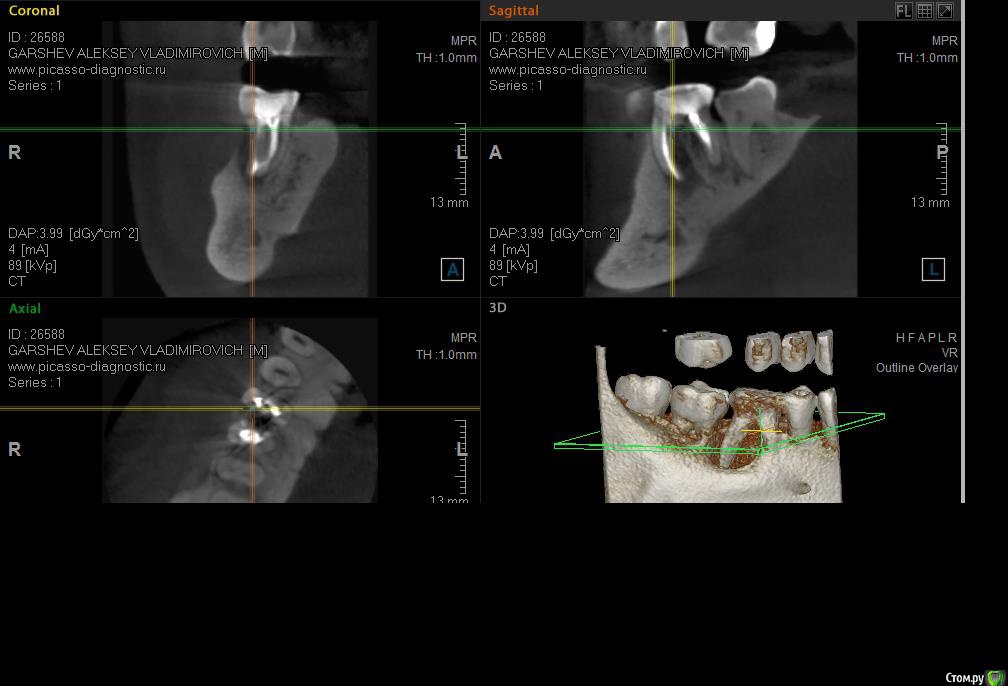

Salma Опубликовано 28 апреля, 2016 Поделиться Опубликовано 28 апреля, 2016 Зуб лечен раньше биологическим методом ( как показало вскрытие), периодически появлялся свищ, но, как утверждает пациент, зуб особых беспокойств не доставлял. Пролечили, кальций на две недели, потом постоянная пломбировка.Картина такая: Ссылка на комментарий

ger_berra Опубликовано 5 мая, 2016 Поделиться Опубликовано 5 мая, 2016 Зуб лечен раньше биологическим методом ( как показало вскрытие), периодически появлялся свищ, но, как утверждает пациент, зуб особых беспокойств не доставлял. Пролечили, кальций на две недели, потом постоянная пломбировка.Картина такая:Оси на КТ выставлены не корректно.Свищ где именно появлялся? Зуб красили на предмет трещины? Ответ " примерно до уровня бифуркации" не информативен. Ссылка на комментарий